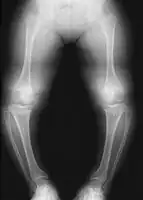

Radiologic findings

A skeletal survey is useful to confirm the diagnosis of achondroplasia. The skull is large, with a narrow foramen magnum, and relatively small skull base. The vertebral bodies are short and flattened with relatively large intervertebral disk height, and there is congenitally narrowed spinal canal. The iliac wings are small and squared, with a narrow sciatic notch and horizontal acetabular roof.[15][16] The tubular bones are short and thick with metaphyseal cupping and flaring and irregular growth plates.[15] Fibular overgrowth is present. The hand is broad with short metacarpals and phalanges, and a trident configuration. The ribs are short with cupped anterior ends.[15] If the radiographic features are not classic, a search for a different diagnosis should be entertained. Because of the extremely deformed bone structure, people with achondroplasia are often "double jointed". The diagnosis can be made by fetal ultrasound by progressive discordance between the femur length and biparietal diameter by age. The trident hand configuration can be seen if the fingers are fully extended.

Another distinct characteristic of the syndrome is thoracolumbar gibbus in infancy.